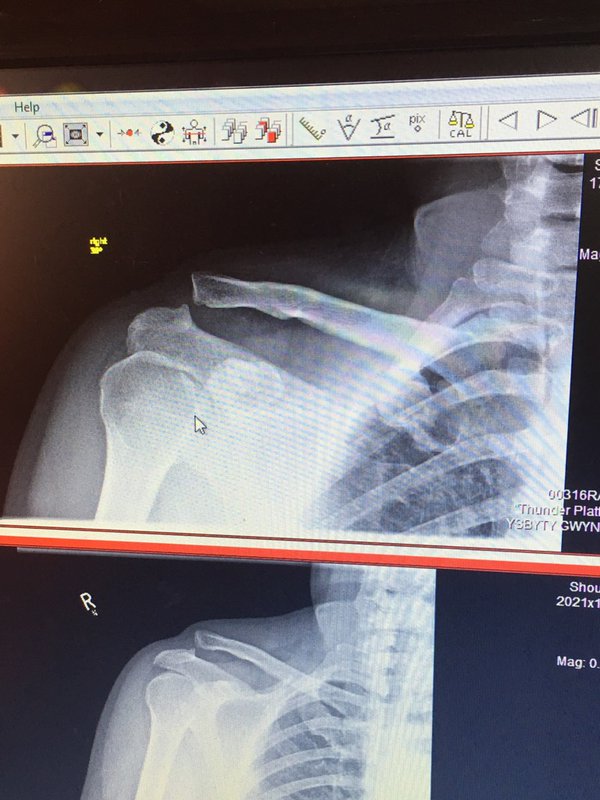

Simon Gregson has tweeted an X-ray of the shoulder injury that has again ruled him out of Corrie after he'd just return from a long lay-off due to stress-related problems.

Simon, 41, is believed to have suffered the injury while he was playing with his sons, Alfie, eight, and Harry, six. The X-ray appears to show a clear break at the point of his shoulder.

The star tweeted an image of the X-ray and wrote cryptically: "Remember when you just used to get a graze a plaster and rub on the head. It's not age it's science."